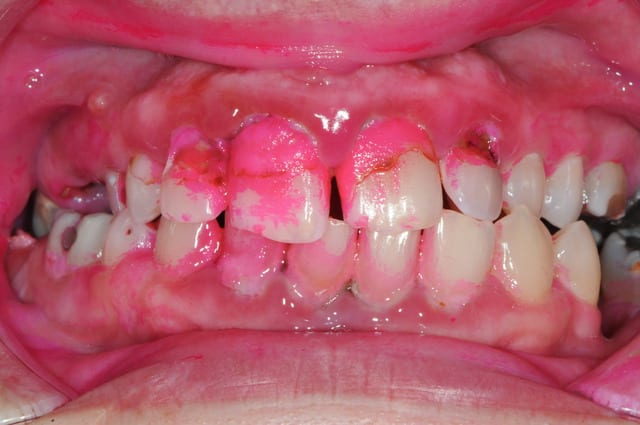

la semaine passée...

-Docteur, les 2 dents du centre bougent...

-Ben, on les enlèvent...

-Je ne peux pas rester sans dent, c'est pas joli...

--